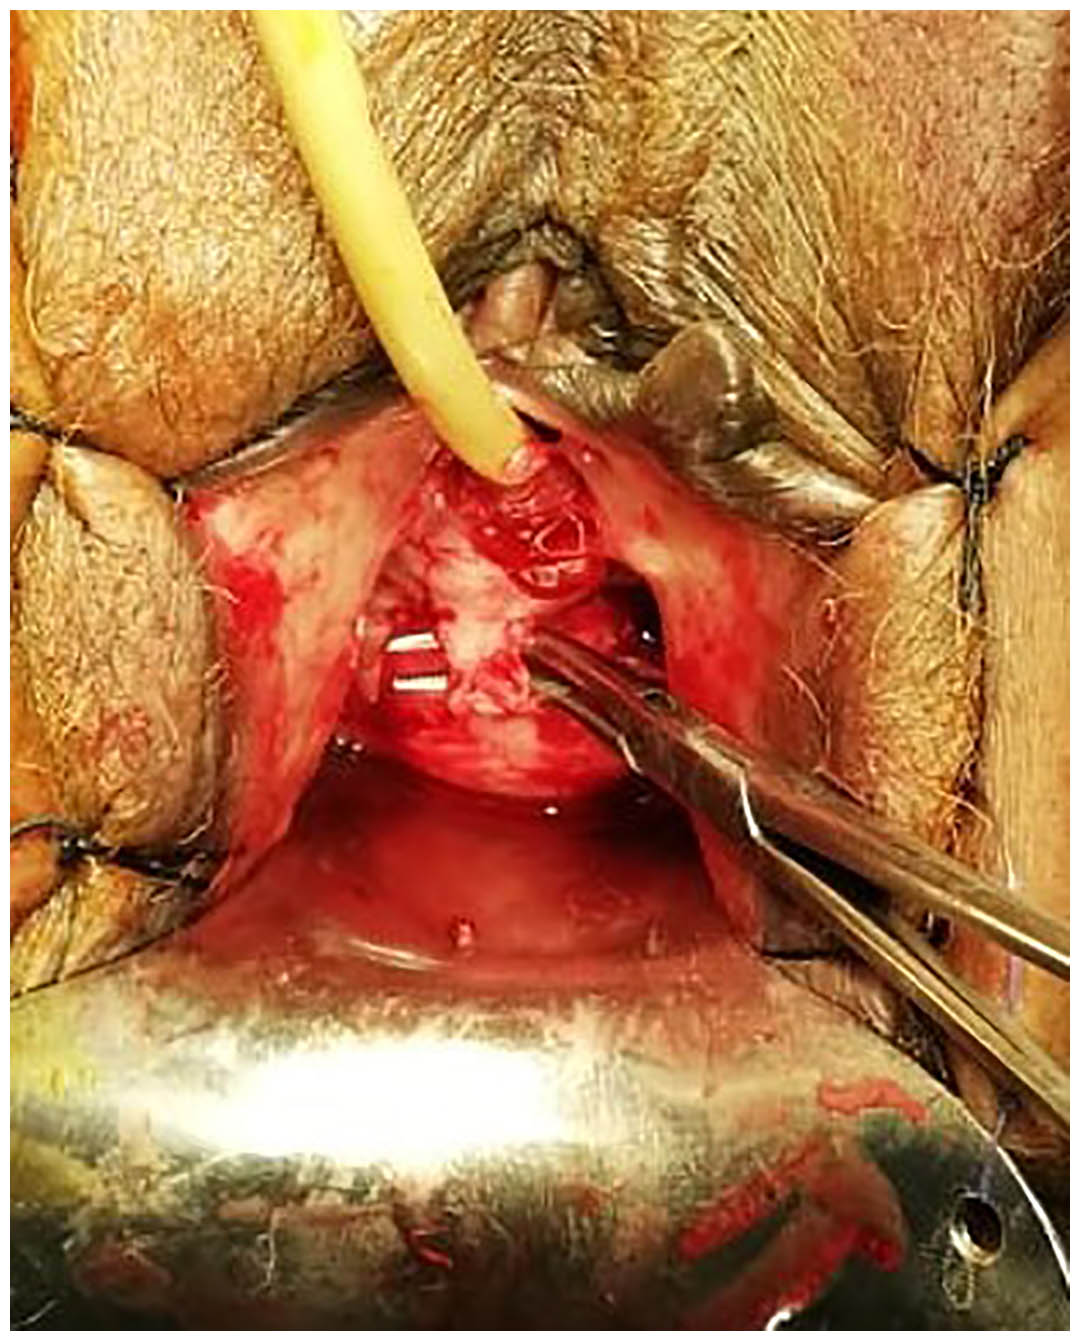

Our technique involves a 2 paramedian incisions in the anterior vaginal wall each is 1cm long in the anterior vaginal wall 2 cm apart parallel to the urethra till identification of the mid urethral portion by palpating the catheter balloon through the vagina then a communication was done between the 2 incision 1 cm wide in this area creating a tunnel to place the tape, with this technique we minimize dissection along the urethra and we keep an island of tissues proximal and distal to the tape to stabilize the tape and avoid tape migration unlike the standard technique with larger tissue dissection at the peri-urethral space that undermine the tape stability later on.